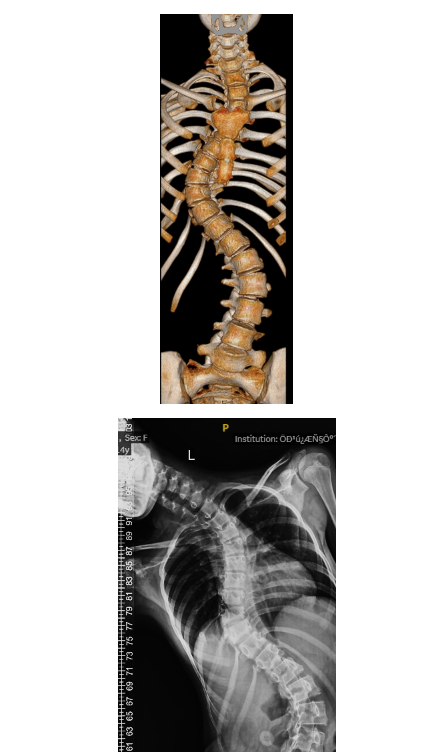

南方puls:14岁少女腰杆扭成麻花,找深圳光明这家医院“撑腰”